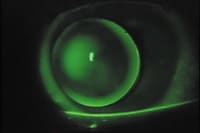

After selecting the appropriate base curve, we focused on bracketing the A value. The peripheral curve asphericity of the ComfortKone more closely aligns with the mid-peripheral conical slope seen in keratoconic patients. We bracketed the peripheral curve radii by incremental steps of 5 until we achieved the best mid-peripheral relationship and edge profile (Figures 4, 5 and 6). Of special note, as Figures 3 and 5 show, once the A values approach the desired fit, small incremental steps of less than 5 can greatly enhance the mid-peripheral pattern and edge lift profile.

Final Fit Maintaining an apical vault, we bracketed the ComfortKone PC (A value) and photodocumented it to show how subtle A value changes affect the overall fit. The successful fit for this patient reveals apical pooling, diffuse mid-peripheral bearing and optimal edge lift, promoting good tear exchange (Figure 3). Snellen visual acuity was 20/20 and the lens demonstrated good movement with adequate centration. The patient reported excellent comfort with the ComfortKone.

Figure 5. A12/6.80mm BC/8.50 OAD. Small incremental steps of less than 5 can greatly enhance the mid-peripheral pattern and edge lift |